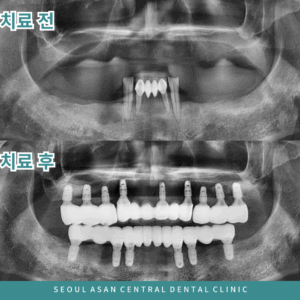

성남치과 전체적으로 임플란트 치료를! 자연치를 한두개가 아닌 여러개를 상실하게 되면 틀니와 인공치아를 고민하게 됩니다. 당장에 불편하기 때문에 치료 기간을 비교하게 되는 경우가 있는데요. 틀니는 치료 기간이 짧은 대신 잇몸이 변화함에…